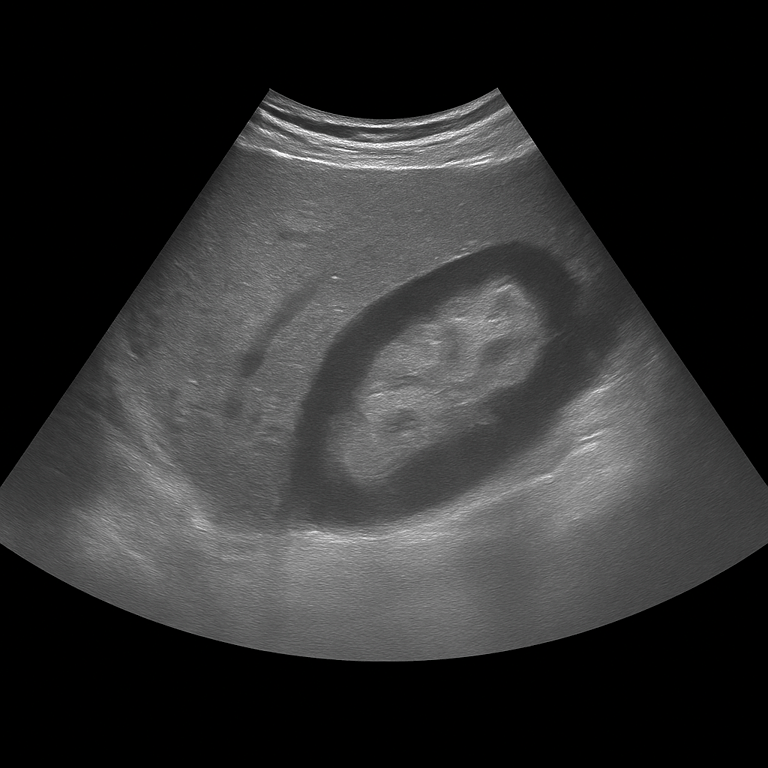

A kidney ultrasound is used to examine the size, shape, tissue structure and blood flow of the kidneys. The examination is performed by a specialist in radiology and provides detailed images in real time that can detect changes that affect kidney function or urine flow. It is used to investigate, among other things, kidney stones, cysts, fluid accumulation, infections or suspected tumors.

Unlike MRI and CT, which are often used for more advanced mapping or suspected tumors, ultrasound is the first-line method for functional and structural assessments. It can be performed without contrast media and shows the kidneys in real time – ideal for detecting stones, cysts or fluid accumulation without the risk of radiation.

Conditions that can be detected with an ultrasound examination of the kidneys

- Fluid accumulation (hydronephrosis) due to blockage in the urinary tract.

- Kidney cysts or multiple cyst formations.

- Changes in the kidney parenchyma in chronic kidney disease.

- Kidney infection (pyelonephritis) with swelling of the kidney tissue.

- Tumor or suspicious mass in the kidney that requires further investigation with MRI or CT.